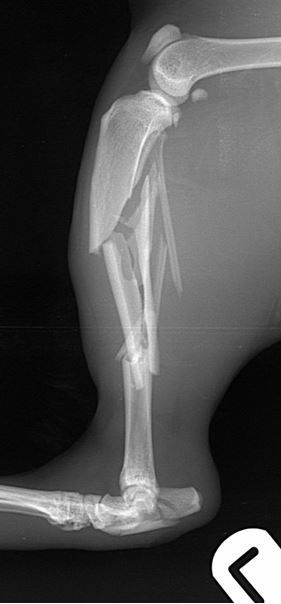

cat with comminuted fractures of the tibia, fibula and calcaneus         cat with comminuted fractures of the tibia, fibula and calcaneus

Fig. 1 A 6-year-old DSH cat with comminuted fractures of the tibia, fibula and calcaneus